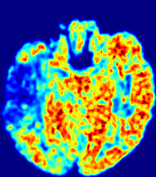

Figure 4: PIANO feature maps for another patient in the ISLES 2017 training set, where the lesion is located in the right hemisphere. Top row: segmented stroke lesion region (white) on different slices. The corresponding slices for the PIANO feature maps are shown in the following rows.

For a better insight into an estimated velocity field 𝐕𝐕{\bf{V}} and diffusion field 𝐃𝐃{\bf{D}}, we compute the following maps: (1) 𝐕rgbsubscript𝐕𝑟𝑔𝑏{\bf{V}}_{rgb}: Color-coded orientation map of 𝐕=(Vx,Vy,Vz)T𝐕superscriptsuperscript𝑉𝑥superscript𝑉𝑦superscript𝑉𝑧𝑇{\bf{V}}=(V^{x},V^{y},V^{z})^{T}, obtained by normalizing 𝐕𝐕{\bf{V}} to unit length and mapping its 3 components to red, green, blue respectively; (2) 𝐕2subscriptnorm𝐕2\|{\bf{V}}\|_{2}: 222 norm of 𝐕𝐕{\bf{V}}; (3) D𝐷D: scalar field in Eq. 5.

Fig. 3 and Fig. 4 show the PIANO feature maps estimated from two ISLES 2017 patients: all are highly consistent with the lesion in both cases. Details of the blood flow trajectories are revealed in 𝐕rgbsubscript𝐕𝑟𝑔𝑏{\bf{V}}_{rgb} by the ridged patterns and the sharp changes of colors in the unaffected (right) hemisphere, while the flat patterns appearing within the lesion provide little directional information about the velocity and indicate low velocity magnitudes. Velocity magnitudes are more directly visualized via 𝐕2subscriptnorm𝐕2\|{\bf{V}}\|_{2}, from which one can easily locate the lesion where 𝐕2subscriptnorm𝐕2\|{\bf{V}}\|_{2} is low. D𝐷D also indicates lower diffusion values in the lesion, though with less contrast potentially due to the fact that it captures the accumulated effect of CA diffusion at the voxel-level.